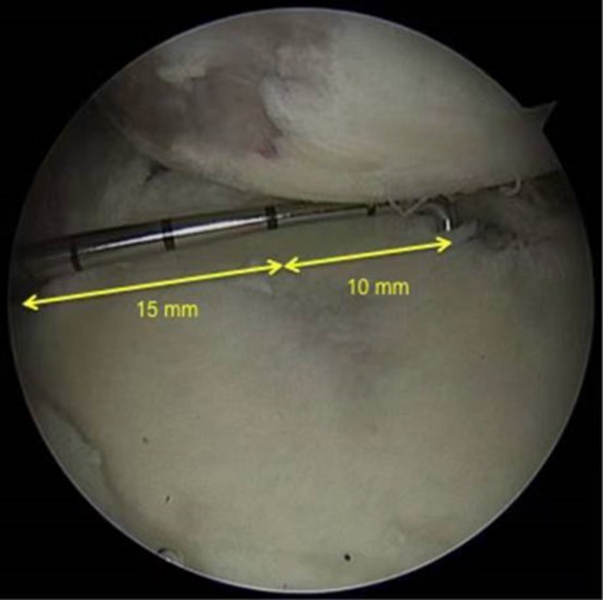

图31 D:15X2=30mm,d:15-10=5mm,83%D=24.9mm,d/D=16.7%

根据公式,可以计算出存在骨缺损的肩胛盂轨迹(0.83D-d),此例中的肩胛盂轨迹为0.83×30-5=19.9mm。

图32 Hill-Sachs损伤测量方式

上图为Hill-Sachs损伤的测量方式,采用前端为4mm的探钩,可以看到Hill-Sachs损伤的区域为3个探钩前端的跨度,因此HS为12mm。

评估报告提示:肩胛盂轨迹(Glenoid Track,GT)19.9mm,Hill-Sachs间距(Hill-Sachs Interval,HSI)24mm。

图34 BB=12

骨桥宽度的测量方式,采用前端为4mm宽的探钩测量,发现骨桥宽度正好为3个探钩前端的跨度,应为12mm。

计算Hill-Sachs间距(Hill-Sachs Interval,HIS)。这个间距应为Hill-Sachs损伤的宽度(HS)加上骨桥(Hill-Sachs损伤的外侧缘到肩袖止点)的宽度(BB),HSI:HS+BB=24mm。